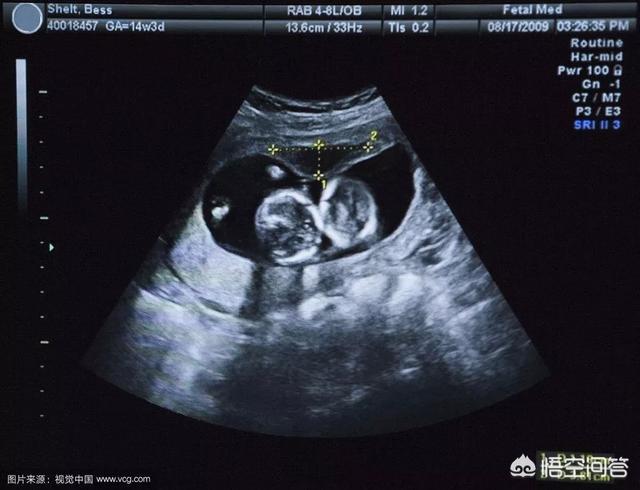

超音波検査で妊娠嚢の位置を確認しますが、妊娠1ヶ月の妊娠嚢は小さすぎて見えないことがあるので、妊娠42日目まで待つことをお勧めします。

妊娠嚢の位置をはっきりさせ、子宮外妊娠やその他の異常を除外するために、再度、婦人科超音波検査を受ける必要があります。 当分の間、妊娠嚢が見えない場合は、後日、再検討することができます!

在経過観察の際には、超音波検査と採血が必要です。採血と超音波検査は通常2~3日以上の間隔で行われますが、子宮外妊娠の発見をより良くするため、また子宮に影響を与えないために、超音波検査が陰性であることが要求されることが多くなります。